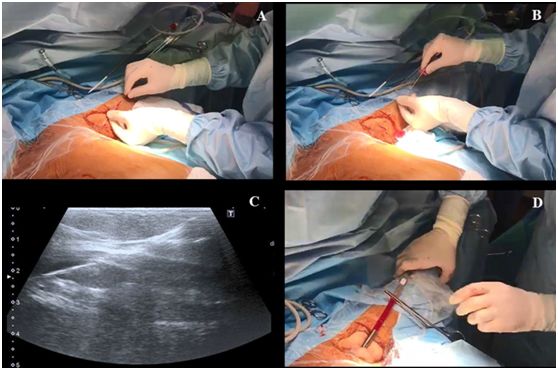

第三步,操作者左手持超声探头,右手持带穿刺针的注射器在超声引导下对腋静脉进行穿刺,超声长轴图像平面内同时可见静脉腔及穿刺针(图2)。皮肤穿刺点尽可能靠近超声探头远端的短边上。当穿刺针触碰到静脉前壁时,在压力的作用下,静脉壁会出现下沉塌陷,因此,此时应快速进针。

当在腋静脉腔内观察到针尖的斜面时(一个白点),可以很容易地确定穿刺针在血管内的位置(图2C)。也可以通过回抽血液1-2ml来确认穿刺针的位置是在静脉内。当患者血压较低时,无搏动性血流出现并不能排除穿刺到动脉的可能。随后置J形导丝,导丝的位置也可能在超声实时下确认(图3,A-C)。也可以通过颈部超声探查来排除导丝进行左侧颈内静脉。导丝置入长度应限定在20cm,以避免引起心律失常。随后扩张皮肤穿刺点,用Seldinger技术置入导管。在输注任何液体之前,回抽确认导管远端是否在血管腔内,随后再用肝素盐水冲洗导管。导管置入深度为20cm。

图2,A 沿超声探头长轴插入穿刺针;B 超声视窗下可见穿刺针进行静脉;C 超声视窗下看到的血管内穿刺针斜面。

图3,A和B置入导丝,C超声视窗下可见静脉的导丝;D 把导管固定